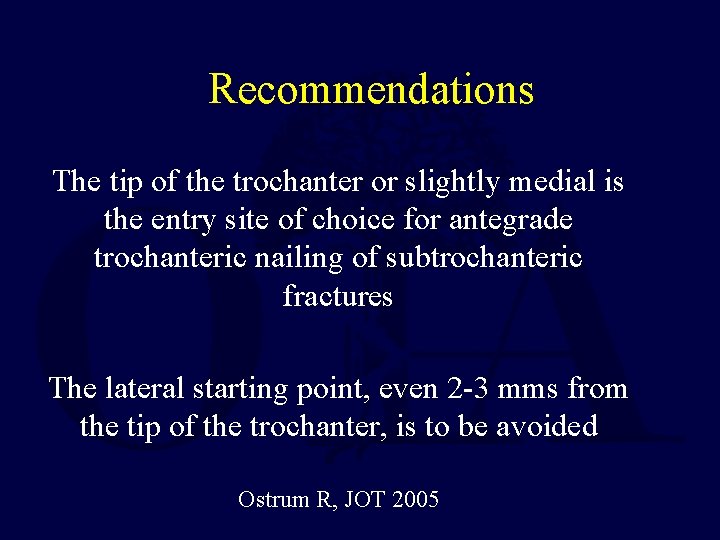

Recommendations The tip of the trochanter or slightly medial is the entry site of choice for antegrade trochanteric nailing of subtrochanteric fractures The lateral starting point, even 2 -3 mms from the tip of the trochanter, is to be avoided Ostrum R, JOT 2005